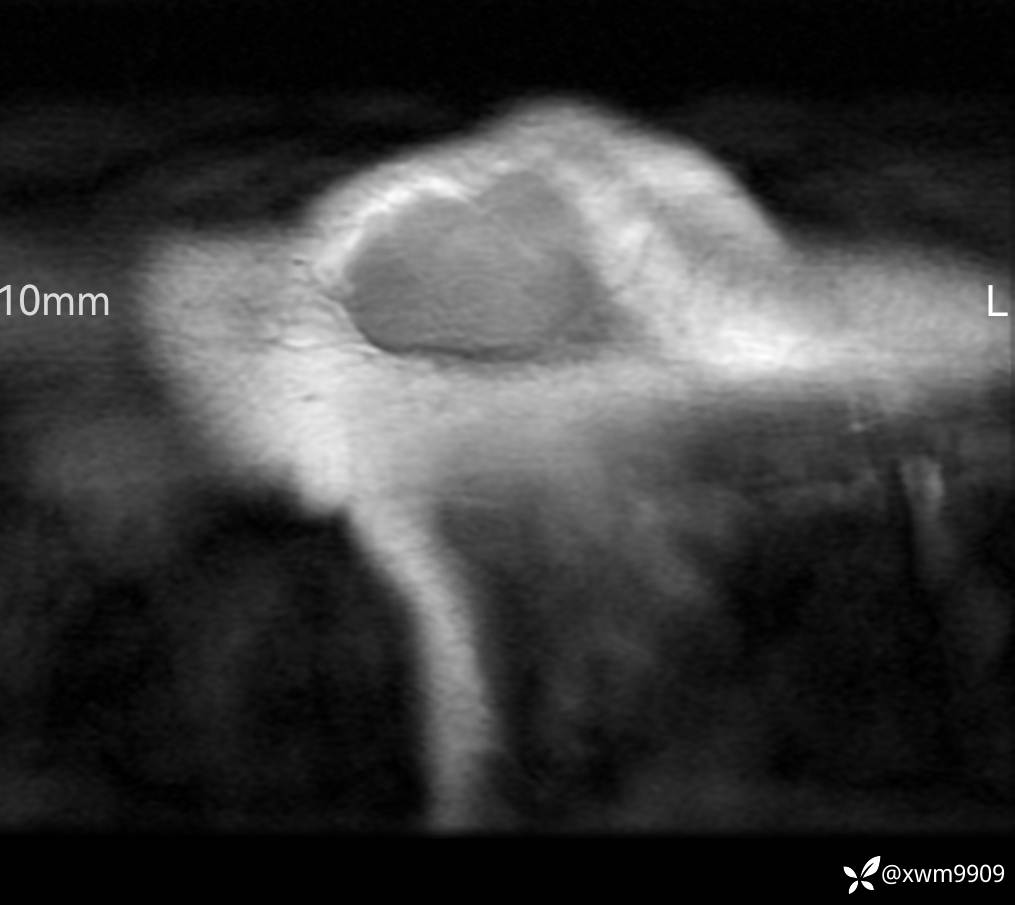

DR:

CT:

2、CT、MR肿块内可见液-液平面,常见有哪些疾病。